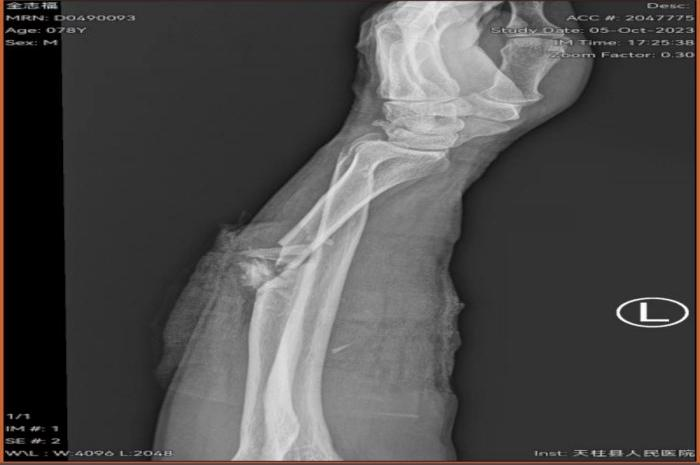

患者金某某,男,78岁,因在家使用电锯锯柴时不慎被电锯锯伤左前臂,血流不止、疼痛难忍,当时患者家属考虑手术难度大希望转诊上级医院治疗但又考虑到转时间过长风险因素高,在左右为难之际,患者一家属联系到天柱县中医院骨科学科带头人、主任医师张平院长,张平院长知悉情况后,征得患者及家属同意,通过急诊120转诊到天柱县中医院并开通绿色通道办理入住到天柱县中医院骨伤科。

在张平院长的带领下,天柱县中医院骨伤科及手术室麻醉科团队建立绿色急诊快速通道经过三个多小时的手术,患者手术满意顺利安返病房。术后患者及家属非常感激,直言天柱县中医院医师敢于担当、技术过硬、为民解忧,在家门口就能解决高难度手术。术后骨伤科医护团队继续为该患者进行专业的专科治疗护理。目前患者已经顺利康复出院了。